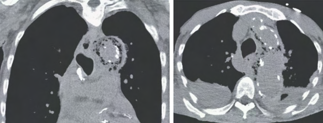

Recent studies indicate that Generative Pre-trained Transformer 4 with Vision (GPT-4V) outperforms human physicians in medical challenge tasks. However, these evaluations primarily focused on the accuracy of multi-choice questions alone. Our study extends the current scope by conducting a comprehensive analysis of GPT-4V's rationales of image comprehension, recall of medical knowledge, and step-by-step multimodal reasoning when solving New England Journal of Medicine (NEJM) Image Challenges - an imaging quiz designed to test the knowledge and diagnostic capabilities of medical professionals. Evaluation results confirmed that GPT-4V outperforms human physicians regarding multi-choice accuracy (88.0% vs. 77.0%, p=0.034). GPT-4V also performs well in cases where physicians incorrectly answer, with over 80% accuracy. However, we discovered that GPT-4V frequently presents flawed rationales in cases where it makes the correct final choices (27.3%), most prominent in image comprehension (21.6%). Regardless of GPT-4V's high accuracy in multi-choice questions, our findings emphasize the necessity for further in-depth evaluations of its rationales before integrating such models into clinical workflows.